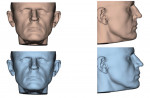

In the case presented, a 59-year-old male patient had severe OSA (AHI 45), decreased posterior airway space, and concomitant maxillofacial skeletal deformities (Angle class II malocclusion, maxillary and mandibular retrognathia, transverse maxillary hypoplasia, and transverse mandibular hypoplasia) (Figure 1 through Figure 4). Orthognathic surgical planning included tracings of a reconstructed lateral cephalogram to estimate postsurgical esthetic changes after advancements of 8 mm, 10 mm, and 12 mm (Figure 5). It is important to note that facial esthetics may change significantly, and this must be discussed in detail with the patient.

Virtual surgical planning in this case is demonstrated in Figure 6 through Figure 9: preoperative 3D CT imaging and planned surgical bony changes (Figure 6), preoperative 3D CT imaging and planned surgical soft-tissue changes (Figure 7), and examples of prefabricated cutting guides (Figure 8) and plates/screws for the maxilla (Figure 9). Careful attention must be paid to the root apices of the upper posterior and lower anterior teeth, the position of the inferior alveolar nerve and mental foramen, and any potential bony interferences after the reposition of the maxilla and mandible.